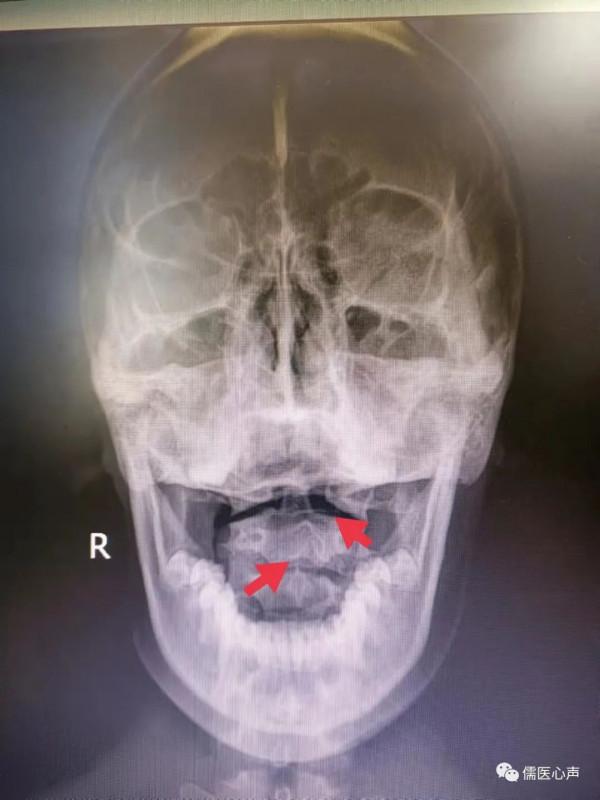

當患者來筆者處就診時,根據其症狀描述和詳細的指下查體(環椎左側移位,環椎左側橫突尖壓痛明顯,樞椎棘突左偏,頸2/3右側關節突關節凹凸感明顯,壓痛明顯),患者病因已基本瞭然,小美女最大的病因嫌疑就是環樞椎錯位誘發的頸源性眩暈,接下來的頸椎張口位X片證實了筆者的判斷,見下圖。

病因清楚了,接下來的就是治療,筆者採用的是非針非藥的美式整脊手法,美式整脊手法的基礎就是脊柱小關節半脫位,再輔以影像學的導引及指下查體後定點定位,極大的提高了治療的安全性、靶向性。在接下來的四聲彈響之後,起身後的小美女眩暈症狀係數消失,這也讓旁觀的中醫學生們大為驚奇。詳細的為她們講解了四聲彈響的來源,學生們心中豁然開朗。

第一聲彈響來源於環椎的復位,發力點位於左側環椎橫突尖;第二聲彈響來源於樞椎椎體的復位,發力點位於頸2/3右側關節突關節處;第三及第四聲彈響準確的說,不是兩聲彈響,而是兩串彈響,來源於頸3至6椎間關節的調整性復位彈響,發力點分別位於兩側的頸4/5關節突關節。經過一系列的手法復位後,小美女的頸椎關節得到復位,對椎動脈的刺激卡壓解除,顱內供血得到改善,眩暈症狀消除也就是自然而然的事情了。